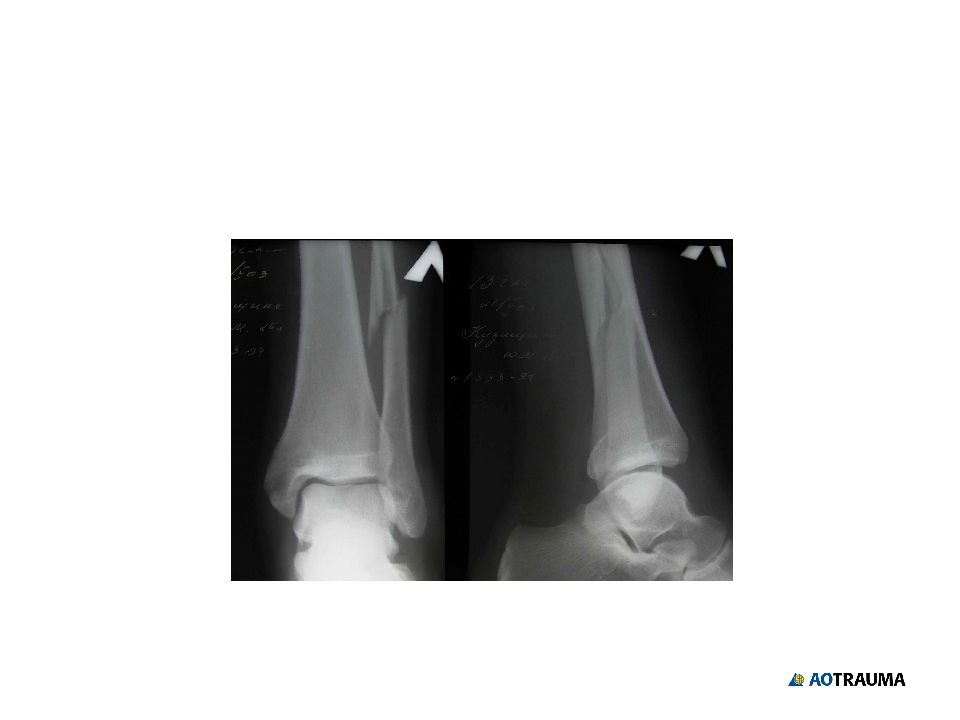

Слайд 23: Четвертый сегмент голени: Лодыжки

А В С подсиндесмозный или синдесмозный? чрессиндесм. или надсиндесмозный?

Изображение слайда